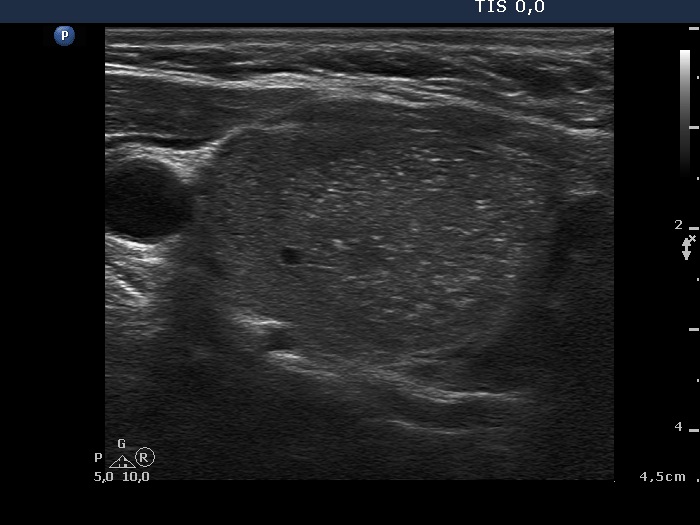

Ultrasonography. The right lobe was moderately hypoechoic while the left was echonormal. A large, less hypoechoic nodule occupied almost the entire right lobe. The nodule presented many hyperechogenic granules and line which corresponded to fibrosis. There were multiple small hypoechogenic lesions in the left lobe.